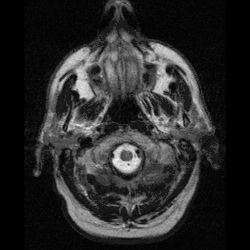

| Cerebellum and basal ganglia | |

Neuroimaging

Neuroferritinopathy is most commonly diagnosed using MRI and other neuroimaging techniques.[1] MRIs help identify the iron deposits in the cerebellum, basal ganglia, and motor cortex common to neuroferritinopathy.[8] MRIs of affected individuals also show mild cerebellar and cerebral atrophy, or tissue breakdown, and gas cavity formation in the putamen.[8] Most importantly, the MRIs show misfolded ferritin proteins and iron deposits in the glial cells of the caudate, putamen, globus pallidus, cerebral cortex, thalamus, and purkinje cells, causing neuronal death in these areas.[8]